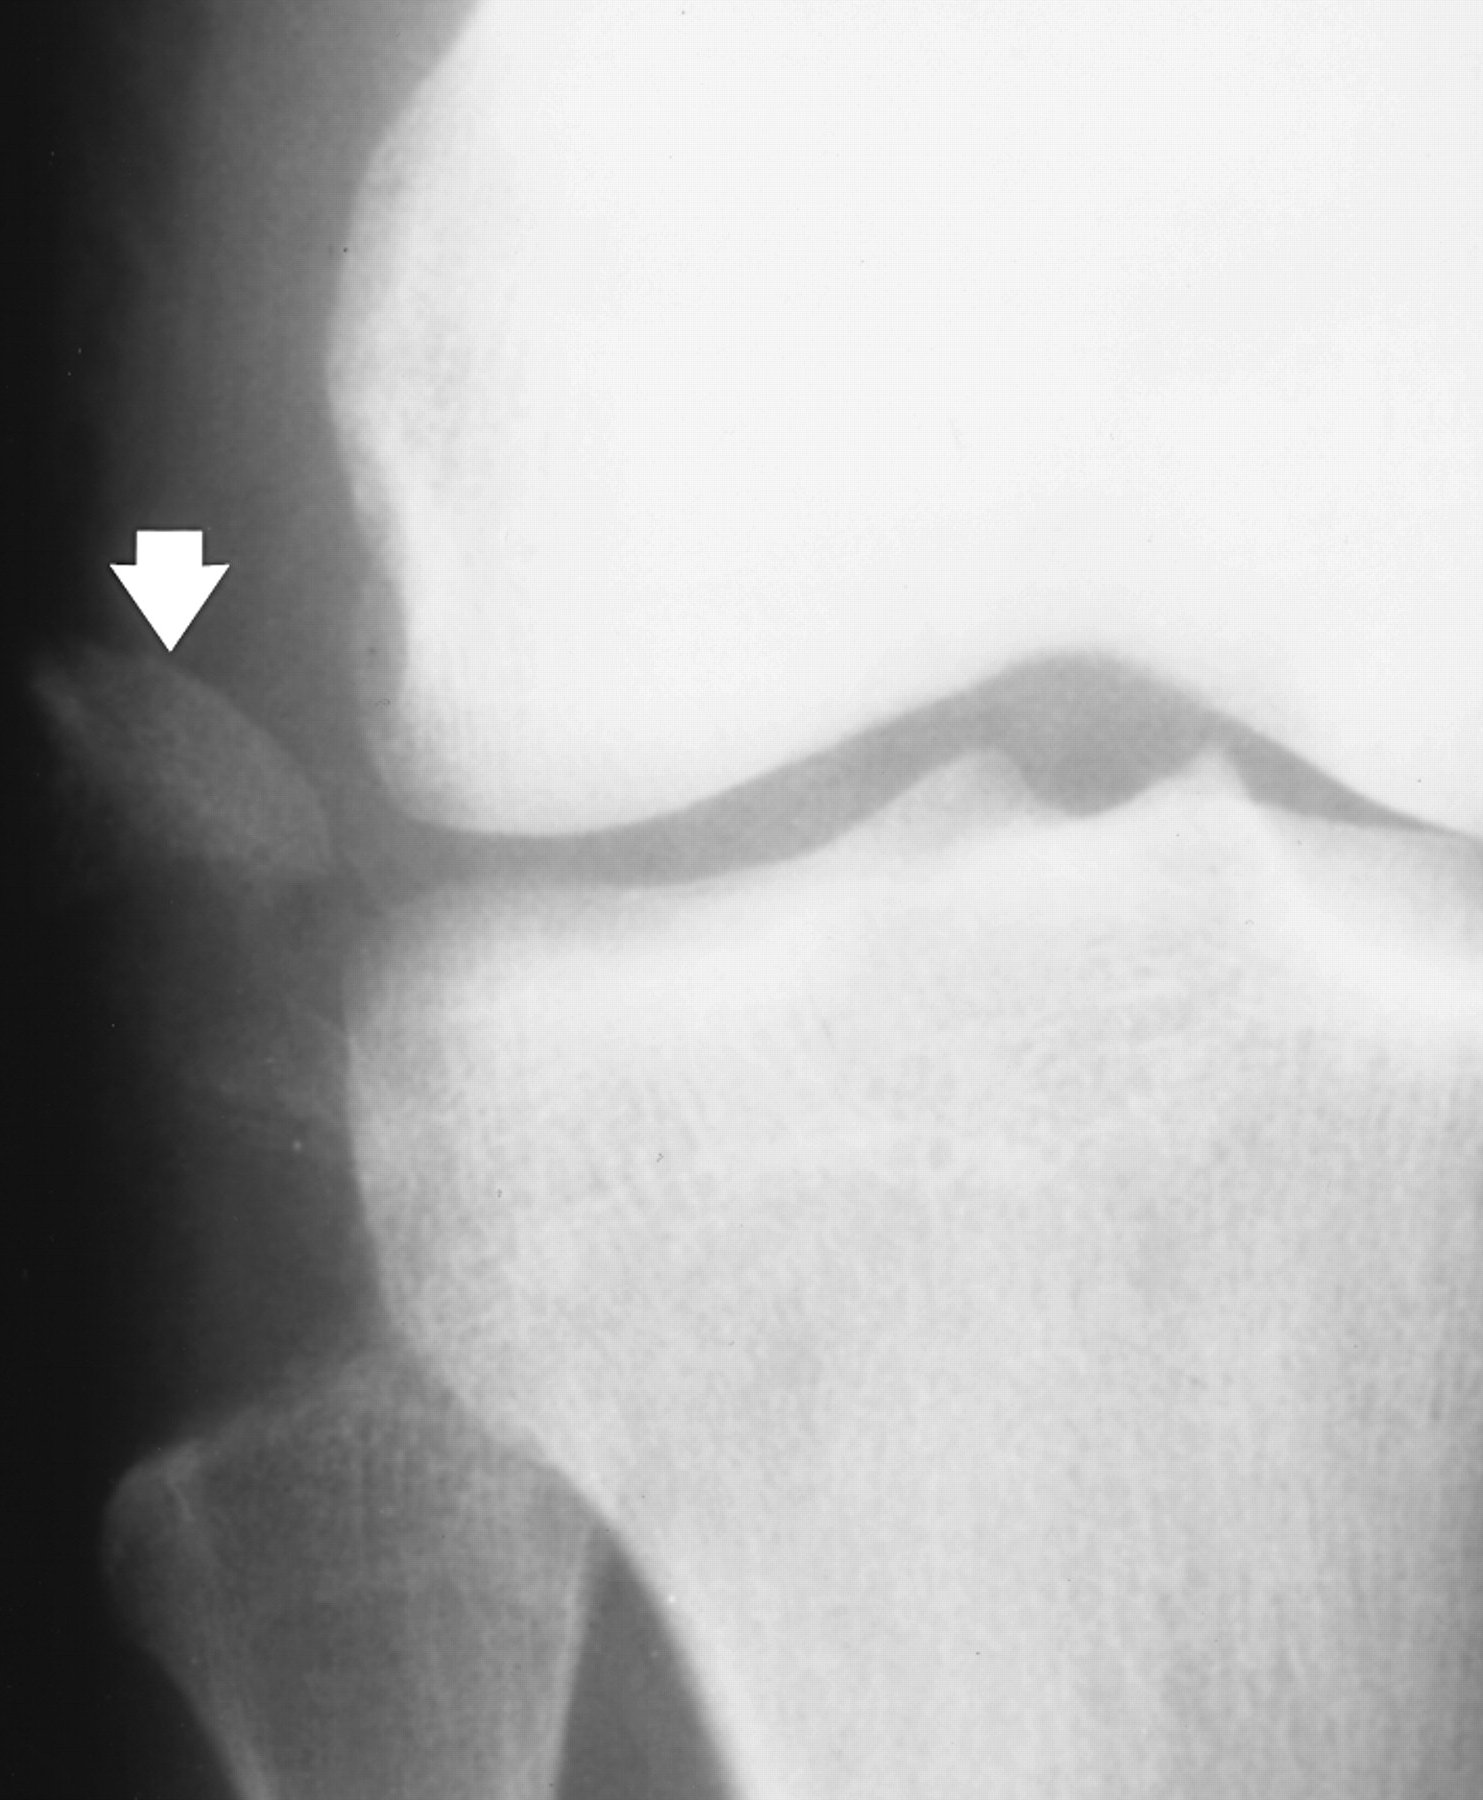

Avulsion fractures are common and easily missed. This may involve the lateral epicondyle, a Segond capsular avulsion or occasionally there is a tell tale avulsion of the tip of the fibular head indicating distraction of the lateral ligaments, this is termed the "Arcuate sign".